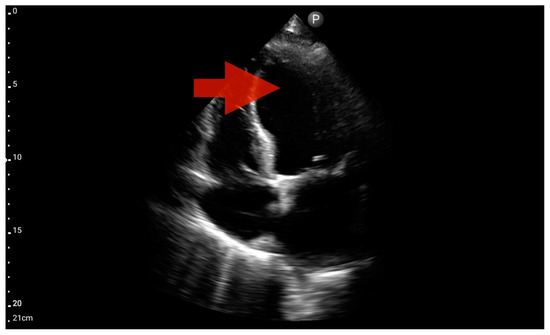

Figure 13.

Right ventricle enlargement; position: parasternal long axis (FATE protocol). Sector probe; the right ventricle is marked with the red arrow, and a significant enlargement of the right ventricle is visible, with a shift of the interventricular septum towards the left ventricle, and an ultrasound picture suggesting pulmonary embolism (source: author’s material—DK).